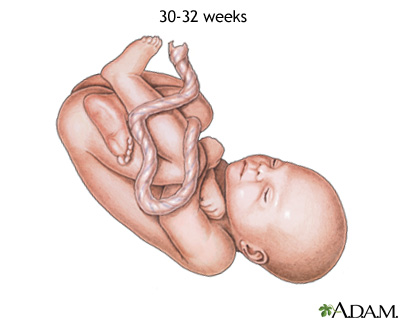

Weeks 27 to 30

- Your baby's brain grows rapidly.

- The nervous system is developed enough to control some body functions.

- Your baby's eyelids can open and close.

- The respiratory system, while immature, produces surfactant. This substance helps the air sacs fill with air.

Weeks 31 to 34

- Your baby grows quickly and gains a lot of fat.

- Rhythmic breathing occurs, but baby's lungs are not fully mature.

- Your baby's bones are fully developed, but are still soft.

- Your baby's body begins storing iron, calcium, and phosphorus.